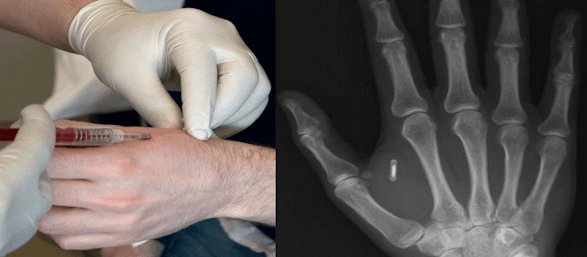

world Jewish leader. If he does these things and is fully successful, rebuilds the Third Temple on its location, and gathers the exiled Jews, he is beyond doubt the Messiah. But if he is not fully successful, or if he is killed, he is not the Messiah. According to Maimonides, Jesus was killed; therefore, He couldn't be the Messiah. There is a problem with this method of proving if a particular person is the messiah. Should you wait before you follow Him until you are convinced that He has successfully fulfilled all of the qualifications of messiah or is killed? What if you follow him and he turns out to be an evil impostor? What if He is the Messiah, and you hesitate to follow Him until you feel sure? Either way you have made a mistake. The False ProphetRevelation 13:11-12 And I beheld another beast coming up out of the earth; and he had two horns like a lamb, and he spake as a dragon. And he exerciseth all the power of the first beast before him, and causeth the earth and them which dwell therein to worship the first beast, whose deadly wound was healed. I don't think there is an antichrist and a false prophet. I think the false prophet is the antichrist. The beast with seven heads and ten horns that comes first is the government itself. The antichrist / false prophet comes after to usurp the kingdom and exercise all the power of the first beast. The beast has only ever had one head at a time. Whenever one head would die, another would rise up to take its place. But when the Roman empire, the sixth head fell, it was as if the beast had died. I saw one of his heads as it were wounded to death...Revelation 13:3. Revelation 17:9 And here is the mind which hath wisdom. The seven heads are seven mountains, on which the woman sitteth. Not Rome. The seven mountains are seven periods of time. Revelation 17:10 And there are seven kings: five are fallen, and one is, and the other is not yet come; and when he cometh, he must continue a short space. [The Beast] one is: Rome the other is not yet come: new world order Revelation 17:11 And the beast that was, and is not, even he is the eighth, and is of the seven, and goeth into perdition. He is an eighth and is of the seven: the antichrist/false prophet becomes king of the seventh head Revelation 17:12 And the ten horns which thou sawest are ten kings, which have received no kingdom as yet; but receive power as kings one hour with the beast. The final head of the beast is a confederation of ten, with ten individual governors. Daniel 7:23-25 Thus he said, The fourth beast shall be the fourth kingdom upon earth, which shall be diverse from all kingdoms, and shall devour the whole earth, and shall tread it down, and break it in pieces. And the ten horns out of this kingdom are ten kings that shall arise: and another shall rise after them; and he shall be diverse from the first, and he shall subdue three kings. And he shall speak great words against the most High, and shall wear out the saints of the most High, and think to change times and laws: and they shall be given into his hand until a time and times and the dividing of time. Daniel 7:24 And the ten horns out of this kingdom are ten kings that shall arise: and another shall rise after them; and he shall be diverse from the first, and he shall subdue three kings. He shall subdue three kings: three of the ten horns are overtaken by an eleventh horn, thereby leaving them eight horns. Revelation 17:11 ...he is the eight, and is of the seven,... The eighth horn becomes the king of the seventh head. "If they build it, he will come." The Anti-MessiahThe Bible says there is an impostor coming to rule the world a few years prior to the return of Jesus Christ. II Thessalonians 2:1-12 Now we beseech you, brethren, by the coming of our Lord Jesus Christ, and by our gathering together unto him, That ye be not soon shaken in mind, or be troubled, neither by spirit, nor by word, nor by letter as from us, as that the day of Christ is at hand. Let no man deceive you by any means: for that day shall not come, except there come a falling away first, and that man of sin be revealed, the son of perdition; Who opposeth and exalteth himself above all that is called God, or that is worshipped; so that he as God sitteth in the temple of God, shewing himself that he is God. Remember ye not, that, when I was yet with you, I told you these things? And now ye know what withholdeth that he might be revealed in his time. For the mystery of iniquity doth already work: only he who now letteth will let, until he be taken out of the way. And then shall that Wicked be revealed, whom the Lord shall consume with the spirit of his mouth, and shall destroy with the brightness of his coming: Even him, whose coming is after the working of Satan with all power and signs and lying wonders, And with all deceivableness of unrighteousness in them that perish; because they received not the love of the truth, that they might be saved. And for this cause God shall send them strong delusion, that they should believe a lie: That they all might be damned who believed not the truth, but had pleasure in unrighteousness. In the book of Daniel, Nebuchadnezzar, the king of Babylon, had a dream of a giant statue whose various body parts represented empires that would rule the world until the end of time. Daniel 2:41-45 And whereas thou sawest the feet and toes, part of potters’ clay, and part of iron, the kingdom shall be divided; but there shall be in it of the strength of the iron, forasmuch as thou sawest the iron mixed with miry clay. And as the toes of the feet were part of iron, and part of clay, so the kingdom shall be partly strong, and partly broken. And whereas thou sawest iron mixed with miry clay, they shall mingle themselves with the seed of men: but they shall not cleave one to another, even as iron is not mixed with clay. And in the days of these kings shall the God of heaven set up a kingdom, which shall never be destroyed: and the kingdom shall not be left to other people, but it shall break in pieces and consume all these kingdoms, and it shall stand for ever. Forasmuch as thou sawest that the stone was cut out of the mountain without hands, and that it brake in pieces the iron, the brass, the clay, the silver, and the gold; the great God hath made known to the king what shall come to pass hereafter: and the dream is certain, and the interpretation thereof sure. Psalm 118:22 The stone which the builders refused is become the head stone of the corner. That “stone cut out of the mountain without hands” is Jesus Christ, the Messiah, coming to “…break in pieces and consume all these kingdoms.” Daniel had his own revelations of the end time. The ten toes of Nebuchadnezzar’s dream correspond to the ten horns in Daniel’s vision. Daniel 7:19-28 Then I would know the truth of the fourth beast, which was diverse from all the others, exceeding dreadful, whose teeth were of iron, and his nails of brass; which devoured, brake in pieces, and stamped the residue with his feet; And of the ten horns that were in his head, and of the other which came up, and before whom three fell; even of that horn that had eyes, and a mouth that spake very great things, whose look was more stout than his fellows. I beheld, and the same horn made war with the saints, and prevailed against them; Until the Ancient of days came, and judgment was given to the saints of the most High; and the time came that the saints possessed the kingdom. Thus he said, The fourth beast shall be the fourth kingdom upon earth, which shall be diverse from all kingdoms, and shall devour the whole earth, and shall tread it down, and break it in pieces. And the ten horns out of this kingdom are ten kings that shall arise: and another shall rise after them; and he shall be diverse from the first, and he shall subdue three kings. And he shall speak great words against the most High, and shall wear out the saints of the most High, and think to change times and laws: and they shall be given into his hand until a time and times and the dividing of time. But the judgment shall sit, and they shall take away his dominion, to consume and to destroy it unto the end. And the kingdom and dominion, and the greatness of the kingdom under the whole heaven, shall be given to the people of the saints of the most High, whose kingdom is an everlasting kingdom, and all dominions shall serve and obey him. Hitherto is the end of the matter. As for me Daniel, my cogitations much troubled me, and my countenance changed in me: but I kept the matter in my heart. The horns represent kings. This passage speaks of "ten kings that shall arise" and of “another” that will arise after them. These ten kings prepare the world for the coming of antichrist. Jews, and the pagans alike, are looking for a “messiah” who will come when “the times are ripe” and world conditions are right for him. This anti-messiah will “wear out the saints of the most high.” Revelation 13:5-7 And there was given unto him a mouth speaking great things and blasphemies; and power was given unto him to continue forty and two months. And he opened his mouth in blasphemy against God, to blaspheme his name, and his tabernacle, and them that dwell in heaven. And it was given unto him to make war with the saints, and to overcome them: and power was given him over all kindreds, and tongues, and nations. Daniel 11:32-37 And such as do wickedly against the covenant shall he corrupt by flatteries: but the people that do know their God shall be strong, and do exploits. And they that understand among the people shall instruct many: yet they shall fall by the sword, and by flame, by captivity, and by spoil, many days. Now when they shall fall, they shall be holpen with a little help: but many shall cleave to them with flatteries. And some of them of understanding shall fall, to try them, and to purge, and to make them white, even to the time of the end: because it is yet for a time appointed. And the king shall do according to his will; and he shall exalt himself, and magnify himself above every god, and shall speak marvellous things against the God of gods, and shall prosper till the indignation be accomplished: for that that is determined shall be done. Neither shall he regard the God of his fathers, nor the desire of women, nor regard any god: for he shall magnify himself above all. Daniel 8:23-25 And in the latter time of their kingdom, when the transgressors are come to the full, a king of fierce countenance, and understanding dark sentences, shall stand up. And his power shall be mighty, but not by his own power: and he shall destroy wonderfully, and shall prosper, and practise, and shall destroy the mighty and the holy people. And through his policy also he shall cause craft to prosper in his hand; and he shall magnify himself in his heart, and by peace shall destroy many: he shall also stand up against the Prince of princes; but he shall be broken without hand. The True MessiahJesus Christ, the “Prince of princes”, is coming to destroy the “king of fierce countenance.” The true messiah is coming to destroy the false messiah. Christians are not looking for Jesus to return as a man. He has already “been there and done that.” Is there any Biblical evidence that the mission of Messiah would involve death, resurrection, and a later return? Daniel 9:24-27 Seventy weeks are determined upon thy people and upon thy holy city, to finish the transgression, and to make an end of sins, and to make reconciliation for iniquity, and to bring in everlasting righteousness, and to seal up the vision and prophecy, and to anoint the most Holy. Know therefore and understand, that from the going forth of the commandment to restore and to build Jerusalem unto the Messiah the Prince shall be seven weeks, and threescore and two weeks: the street shall be built again, and the wall, even in troublous times. And after threescore and two weeks shall Messiah be cut off, but not for himself: and the people of the prince that shall come shall destroy the city and the sanctuary; and the end thereof shall be with a flood, and unto the end of the war desolations are determined. And he shall confirm the covenant with many for one week: and in the midst of the week he shall cause the sacrifice and the oblation to cease, and for the overspreading of abominations he shall make it desolate, even until the consummation, and that determined shall be poured upon the desolate. Isaiah 53:1-12 Who hath believed our report? and to whom is the arm of the LORD revealed? For he shall grow up before him as a tender plant, and as a root out of a dry ground: he hath no form nor comeliness; and when we shall see him, there is no beauty that we should desire him. He is despised and rejected of men; a man of sorrows, and acquainted with grief: and we hid as it were our faces from him; he was despised, and we esteemed him not. Surely he hath borne our griefs, and carried our sorrows: yet we did esteem him stricken, smitten of God, and afflicted. But he was wounded for our transgressions, he was bruised for our iniquities: the chastisement of our peace was upon him; and with his stripes we are healed. All we like sheep have gone astray; we have turned every one to his own way; and the LORD hath laid on him the iniquity of us all. He was oppressed, and he was afflicted, yet he opened not his mouth: he is brought as a lamb to the slaughter, and as a sheep before her shearers is dumb, so he openeth not his mouth. He was taken from prison and from judgment: and who shall declare his generation? for he was cut off out of the land of the living: for the transgression of my people was he stricken. And he made his grave with the wicked, and with the rich in his death; because he had done no violence, neither was any deceit in his mouth. Yet it pleased the LORD to bruise him; he hath put him to grief: when thou shalt make his soul an offering for sin, he shall see his seed, he shall prolong his days, and the pleasure of the LORD shall prosper in his hand. He shall see of the travail of his soul, and shall be satisfied: by his knowledge shall my righteous servant justify many; for he shall bear their iniquities. Therefore will I divide him a portion with the great, and he shall divide the spoil with the strong; because he hath poured out his soul unto death: and he was numbered with the transgressors; and he bare the sin of many, and made intercession for the transgressors. Psalm 16:10 For thou wilt not leave my soul in hell; neither wilt thou suffer thine Holy One to see corruption. When the Lord Jesus Christ returns there will be no wondering if it is Him. Matthew 24:23-27 Then if any man shall say unto you, Lo, here is Christ, or there; believe it not. For there shall arise false Christs, and false prophets, and shall shew great signs and wonders; insomuch that, if it were possible, they shall deceive the very elect. Behold, I have told you before. Wherefore if they shall say unto you, Behold, he is in the desert; go not forth: behold, he is in the secret chambers; believe it not. For as the lightning cometh out of the east, and shineth even unto the west; so shall also the coming of the Son of man be. Acts 1:6-11 When they therefore were come together, they asked of him, saying, Lord, wilt thou at this time restore again the kingdom to Israel? And he said unto them, It is not for you to know the times or the seasons, which the Father hath put in his own power. But ye shall receive power, after that the Holy Ghost is come upon you: and ye shall be witnesses unto me both in Jerusalem, and in all Judaea, and in Samaria, and unto the uttermost part of the earth. And when he had spoken these things, while they beheld, he was taken up; and a cloud received him out of their sight. And while they looked stedfastly toward heaven as he went up, behold, two men stood by them in white apparel; Which also said, Ye men of Galilee, why stand ye gazing up into heaven? this same Jesus, which is taken up from you into heaven, shall so come in like manner as ye have seen him go into heaven. Mark of the BeastBe careful to choose the genuine Messiah. A mistake will result in grave consequences. The mark of the beast is indicative of the totalitarian nature of the new world order. It means total slavery to the state for anyone who accepts it. God has warned us against pledging our allegiance to this coming United States of Earth. The consequences are eternal. Revelation 14:9-12 …If any man worship the beast and his image, and receive his mark in his forehead, or in his hand, The same shall drink of the wine of the wrath of God, which is poured out without mixture into the cup of his indignation; and he shall be tormented with fire and brimstone in the presence of the holy angels, and in the presence of the Lamb: And the smoke of their torment ascendeth up for ever and ever: and they have no rest day nor night, who worship the beast and his image, and whosoever receiveth the mark of his name. Here is the patience of the saints: here are they that keep the commandments of God, and the faith of Jesus. Strong’s Greek Dictionary mark: 5480. caragma charagma, khar’-ag-mah from the same as 5482; a scratch or etching, i.e. stamp (as a badge of servitude), or scupltured figure (statue):—graven, mark. 5482. carax charax, khar’-ax from charasso (to sharpen to a point; akin to 1125 through the idea of scratching); a stake, i.e. (by implication) a palisade or rampart (military mound for circumvallation in a siege):—trench. 666: 5516. cxv chi xi stigma, khee xee stig’-ma the 22nd, 14th and an obsolete letter (4742 as a cross) of the Greek alphabet (intermediate between the 5th and 6th), used as numbers; denoting respectively 600, 60 and 6; 666 as a numeral:—six hundred threescore and six. 4742. stigma stigma, stig’-mah from a primary stizo (to "stick", i.e. prick); a mark incised or punched (for recognition of ownership), i.e. (figuratively) scar of service:—mark. Or maybe a stick with a needle!